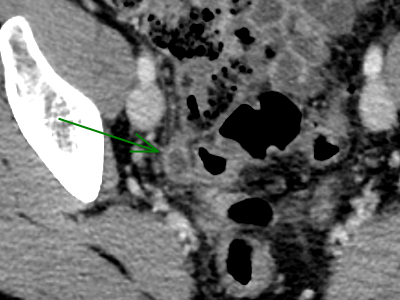

What is the lowest reasonable dose for CT of the appendix? Can we really go lower than 1 mSv?

In general, a lower dose means a lower image quality. The authors have studied the lowest acceptable dose for a reliable analysis of the appendix, for general radiologists and for dedicated specialists. Is it possible to go under 1 mSv? Read this article to find out about the interesting results of this study.

• For both abdominal and non-abdominal radiologists, 1.0-mSv appendiceal CT could be feasible.

• The 0.5-mSv CT was non-inferior to 2.0-mSv CT only for expert abdominal radiologists.